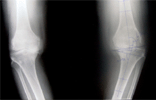

52 year old Malay male with chronic left knee pain due to unicompartmental arthritis

Pre

Op

Pre Operation Xrays